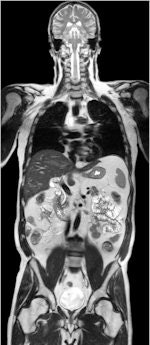

Note: Siemens Healthcare provided the brain MR image used on the home page to illustrate this article.